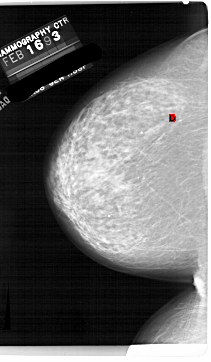

A_1854_1.LEFT_CC

LEFT_CC LINES 6871 PIXELS_PER_LINE 3991 BITS_PER_PIXEL 12 RESOLUTION 43.5 OVERLAY

FILE: A_1854_1.LEFT_CC.OVERLAY

TOTAL_ABNORMALITIES 1

ABNORMALITY 1

LESION_TYPE CALCIFICATION TYPE PLEOMORPHIC DISTRIBUTION CLUSTERED

ASSESSMENT 4

SUBTLETY 2

PATHOLOGY BENIGN

TOTAL_OUTLINES 1

BOUNDARY